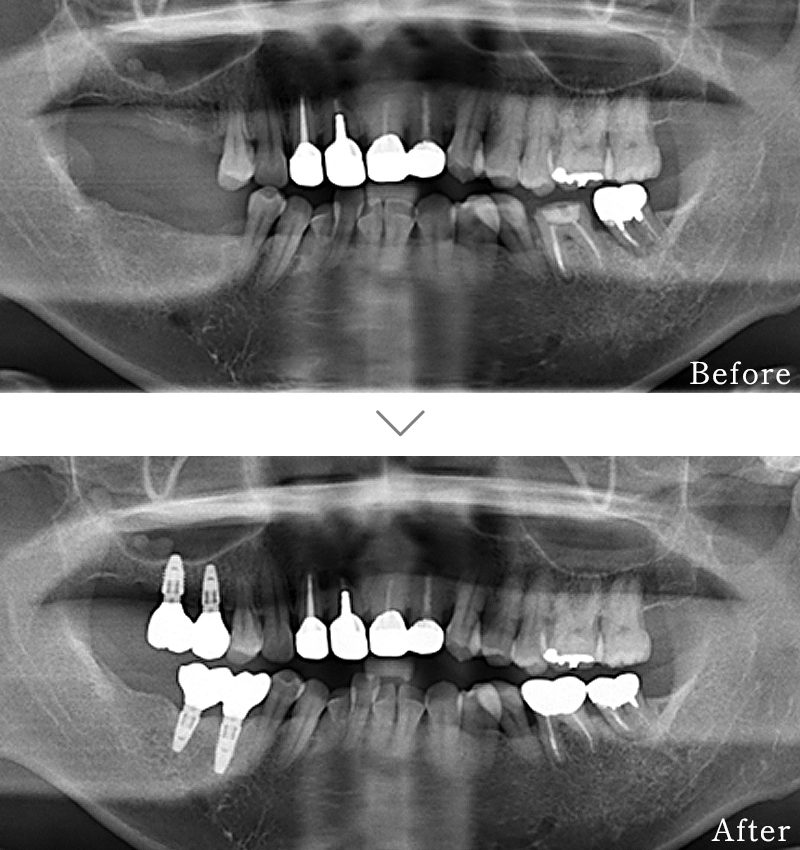

CASE4

主訴 右の奥歯は無くなって食事が噛めない。

治療法 上下2本ずつインプラントを使用して噛み合わせを回復させています。

治療期間 4ヶ月

費用 CT:16,500円(税込)

+ 静脈内鎮静法:66,000円(税込)

+ インプラント治療:2,103,200円(税込)

合計:2,185,700円(税込)